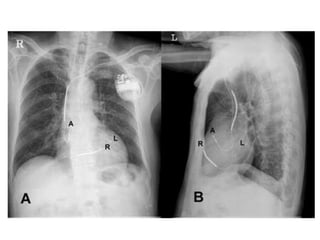

IMPLANTATION PROCEDURE

• Unlike conventional

transvenous pacemaker or

ICD implantation that

requires lead placement in

the right atrium and/or the

right ventricle only, Bi-V

pacing requires LV lead

implantation.

• Initially, this was achieved

via a thoracotomy;

however, currently up to

98% of Bi-V devices are

placed via a transvenous

approach.

• Typically, a cephalic or axillary vein approach to

venous access is used.

• The right atrial and RV leads are implanted in a

fashion similar to a pacemaker or ICD implantation.

• The LV lead is placed through the CS into a CS

branch on the lateral free wall of the left ventricle.

• Performing an occlusive CS venogram may help

identify the appropriate vein.